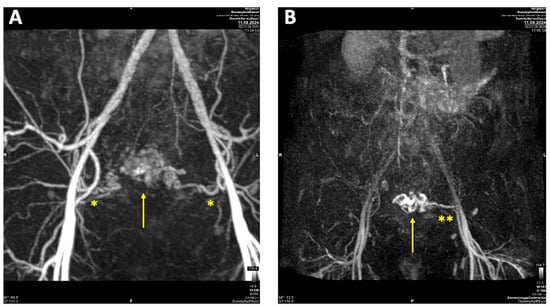

On vaginal examination, no abnormalities or active bleeding were observed. Transvaginal ultrasound revealed a retroflexed uterus measuring 81 × 51 mm, with a suspicious, irregular, hypoechoic, hypervascular lesion measuring 40 × 34 mm on the posterolateral wall of the uterus. This lesion appeared as a prominent vascular tangle extending toward the uterine cavity. Color Doppler sonography demonstrated high-velocity blood flow within the lesion, with a peak systolic velocity (PSV) of 0.3 m/s and a low-resistance pattern, indicated by a resistance index (RI) of 0.43. Distinct arterial and venous blood flow patterns were clearly visualized within the suspicious area (Figure 1 and Figure 2). Both ovaries exhibited normal physiological morphology, appearance, size, and follicle count without abnormalities.

Figure 1. Transvaginal sonography (TVS) Imaging of uterine arteriovenous malformation (AVM): (A) 2D TVS demonstrating a retroflected, enlarged uterus measuring 81 × 51 mm with an inhomogeneous structure in the uterine cavity and fundus; (B) 2D TVS with color Doppler revealing a vascular tangle suggestive of an AVM (arrow); (C) 2D TVS with color Doppler illustrating arterial blood flow within the lesion; (D) 2D TVS with color Doppler depicting venous blood flow in the affected area.